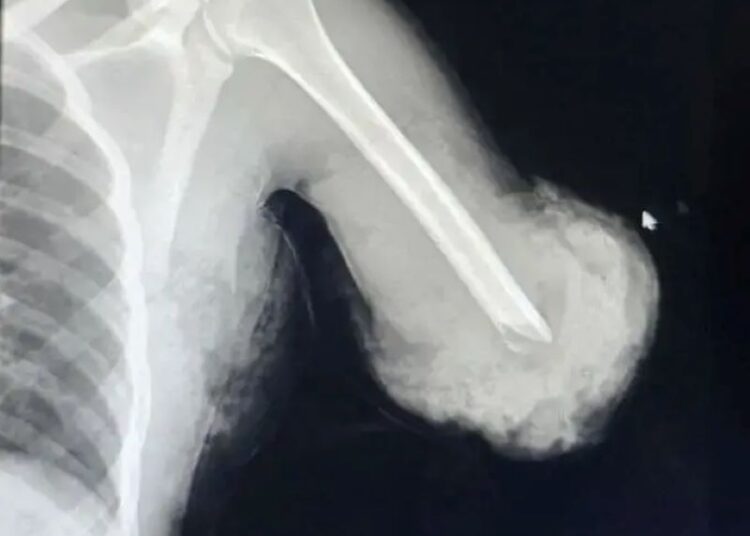

Ibi byabereye ku bitaro byigenga bya Samaritan Surgical Center biherereye i Addis Ababa, aho umusore yakiriwe nyuma y’impanuka yagize akaboko ke kugacikira hejuru y’inkokora mu gihe yakoraga akazi ko gukata imbaho. Dr Anteneh Hailu, umuganga w’inzobere wabigizemo uruhare, yabwiye BBC ko ako kaboko kari katandukanye burundu n’umubiri.

Kubaga kwakozwe mu byiciro bibiri bikomeye. Icyiciro cya mbere cyamaze amasaha atandatu, aho hibanzwe ku gusubiranya igufa n’imitsi minini itwara amaraso, kugira ngo akaboko kongere kubona amaraso no gufatirana n’umubiri. Icyiciro cya kabiri cyabaye nyuma y’ibyumweru bibiri, na cyo kimara hafi amasaha atandatu, hagamijwe kunoza ibisigaye birimo imikaya mito n’udutsi tw’imitsi.

Uyu muganga yasobanuye ko igufa ryacitse rishobora kongera gufatana iyo rihujwe neza, kimwe n’imitsi itwara amaraso ishobora kongera gukora, bigatuma igice cyari cyavuyeho gisubira mu buzima busanzwe buhoro buhoro.